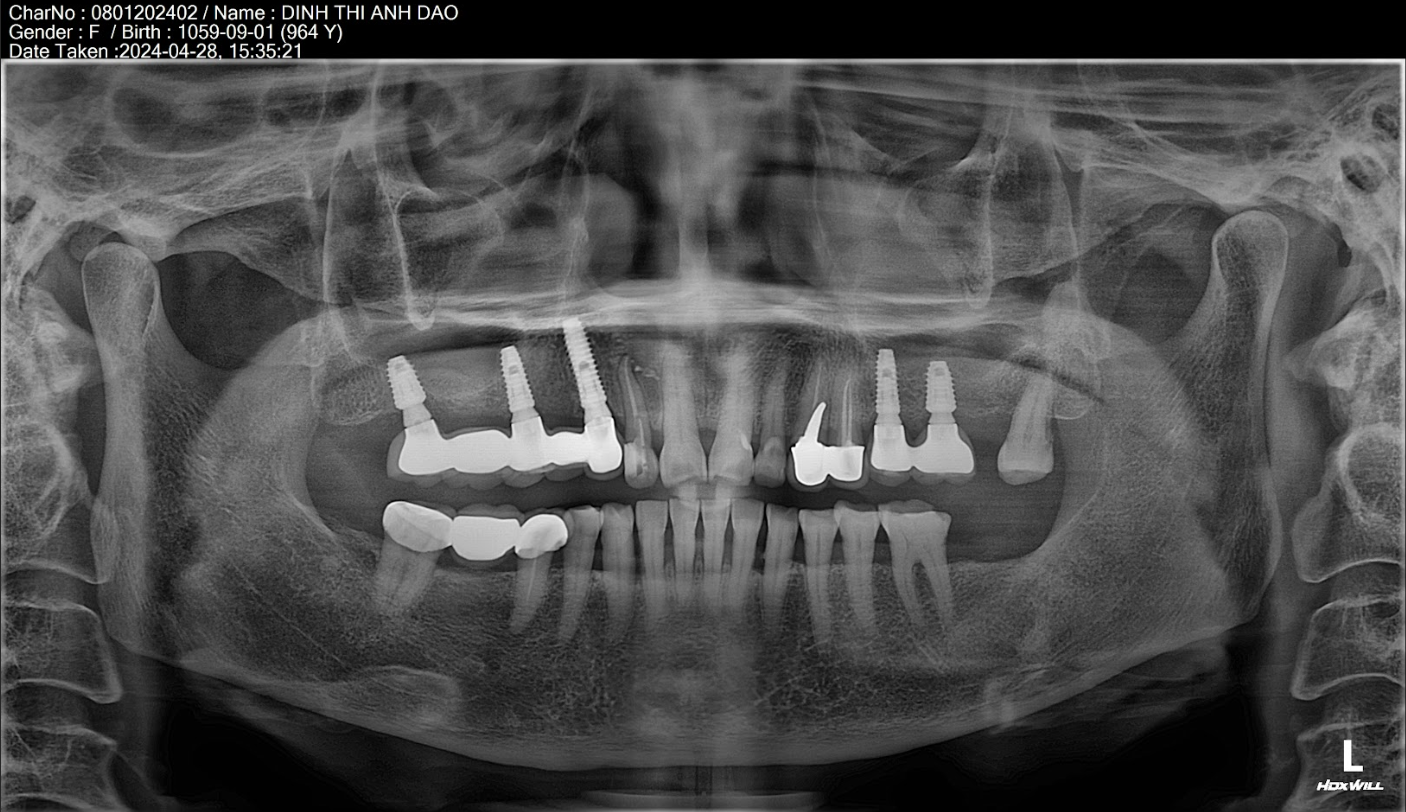

Cô Anh Đào mất 5 răng liên tiếp, nền xương tốt → chỉ cần 3 trụ Dentium Implants.

→ Chi phí: (12.000.000 × 3) + (3.000.000 x 2) = 42.000.000 VNĐ

Nếu xương yếu → bác sĩ đặt 4 trụ, tổng chi phí khoảng 54.000.000 VNĐ.

Cô Đinh Thị Anh Đào có cụm răng mất 5 răng liên tiếp cần trồng 3 trụ, làm 5 răng lên trên